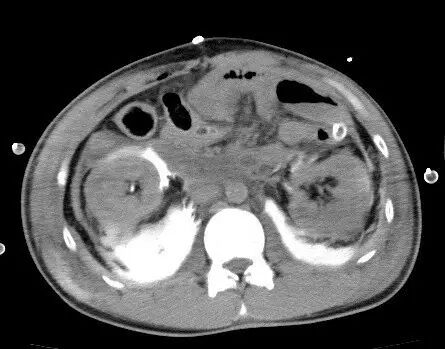

在重症监护室中,患者血压110/60mmHg,心率106次/分,但术后9小时仍未排尿。后行腹部X线检查。肾盂输尿管结合处检测到造影材料渗漏,再次CT发现双侧肾周腹膜后对比度增强(图2)。对其进行膀胱镜检查和双侧逆行肾盂造影,显示双侧输尿管完全破裂,无法植入输尿管支架。诊断性剖腹示双侧肾盂输尿管结合处完全破裂。双侧植入双J输尿管支架,并行肾盂输尿管吻合术。患者术后进展良好,术后第23天出院。

图2